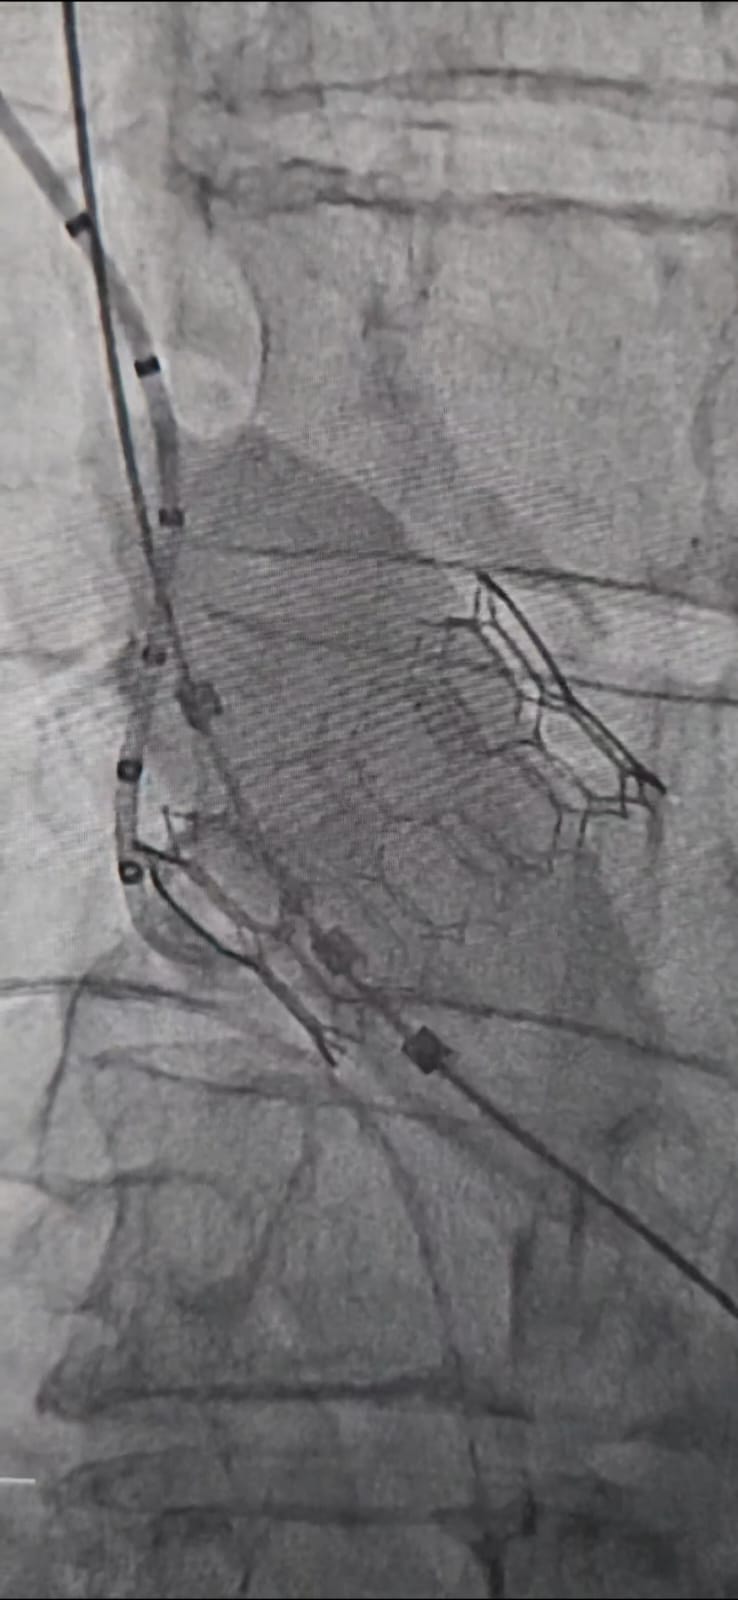

We are thrilled to announce the successful implantation of the MyVal Octacor 32mm at Waikato Hospital, marking a significant milestone in our journey. A huge thanks to Dr. Sanjeevan Pasupati, Dr. Faaez Ali, and the entire Waikato Cathlab team for their unwavering belief and confidence in Octacor. The procedure yielded excellent hemodynamics, underscoring the promising potential of the MyVal Octacor TAVI intermediate and XL sizes. We look forward to achieving more breakthroughs together.

2nd Case at Midland Cardiovascular Services- Hamilton

We at Surgical Supplies are delighted to announce the second successful implantation of the MyVal Octacor 30.5mm at Midland Cardiovascular Services in Hamilton. A heartfelt thank you to Madhav Menon, Dr. Sanjeevan Pasupati, Faeez Mohamad Ali, and the entire MCVS Cathlab team for their steadfast belief in MyVal Octacor. The procedure demonstrated excellent hemodynamic outcomes, highlighting the immense potential of the MyVal Octacor TAVI intermediate and XL sizes. We look forward to more groundbreaking advancements together!